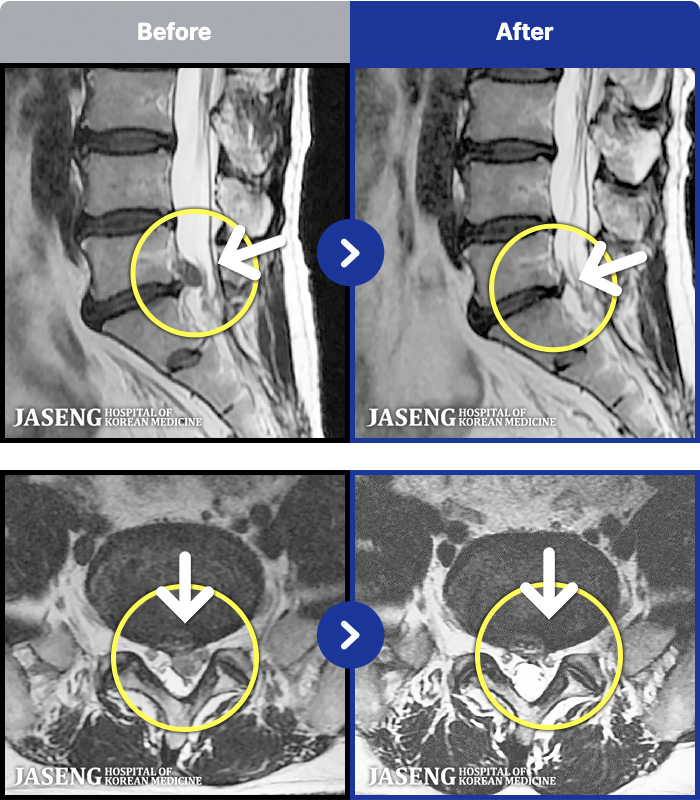

MRI ġ

1,237 MRI ũ ʸ Ȯϼ.